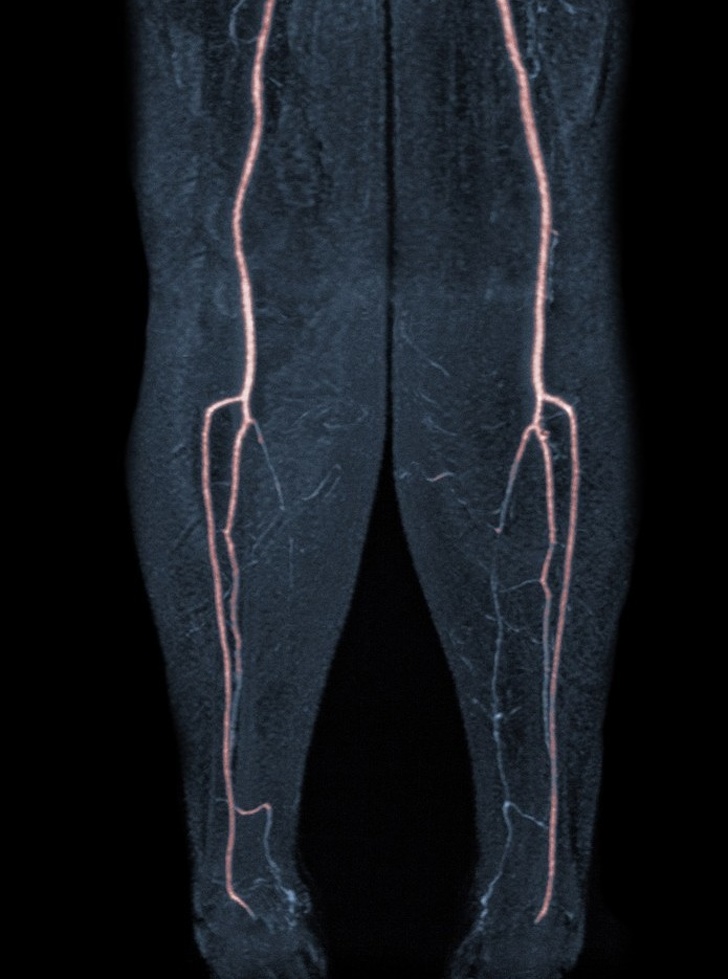

11. Знімок, який засвідчує закупорку судини на лівій нозі